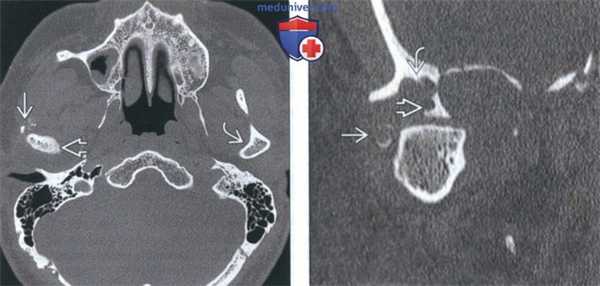

(Слева) На аксиальной КТ без КУ определяется ХС правого мыщелка, снаружи от которого видны множественные плотные включения в отсутствие явного объемного образования. Внутренний край мыщелка склерозирован. Обратите внимание, насколько правый мыщелок отличается от неизмененного левого.

(Справа) На корональной реформатированной КТ без КУ у этого же пациента в мягких тканях визуализируется кольцевидный кальцинат с гиподенсным центром. Определяется деструкция стенок суаавной ямки и большого крыла клиновидной кости. Мыщелок увеличен.

(Слева) На сагиттальной МРТ (Т1 ВИ) у этого же пациента вокруг мыщелка визуализируется многокамерное объемное образование, вовлекающее суставную ямку и большое крыло клиновидной коои.

(Справа) На аксиальной MPT (Т1 ВИ С+ FS) у этого же пациента определяется обширное контрааное усиление солидного объемного образования, окружающего мыщелок, что позволяет исключить его воспалительный характер.

(Слева) На аксиальной МРТ (Т2ВИ FS) у пациента с ХС левого ВНЧС определяется мягкотканный компонент с неоднородным, но в целом высокоинтенсивным Т2 сигналом, типичным для хондроидных опухолей. Точечные гипоинтенсивные очаги отражают внутриопухолевые кальцинаты.

(Справа) На корональной МРТ (Т1ВИС+ FS) у этого же пациента определяется интенсивное накопление контраста в объемном образовании сустава, что подтверждает его солидную структуру и позволяет исключить жидкость в суставе, растягивающую капсулу.